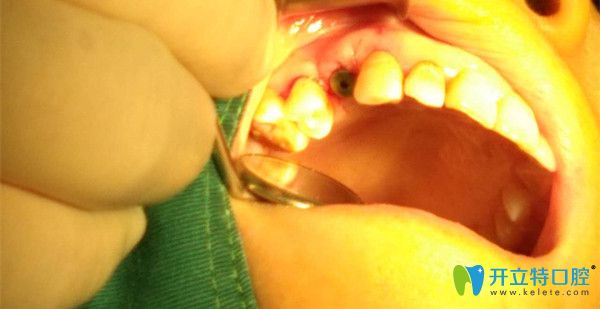

吳為我做手術(shù)中

種牙過(guò)程中的放大圖